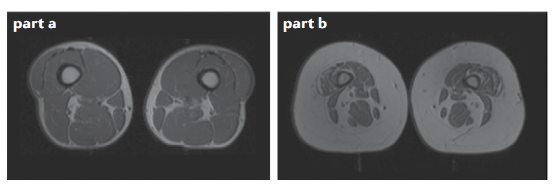

大众很容易将肌少症与 “老来瘦” 联系在一起,但是身材适中甚至偏胖的中老年人也有可能患肌少症,有些人看起来“状”,只是因为皮下脂肪代替肌肉,撑起了身体轮廓。

图注:a. 肌肉 b. 脂肪